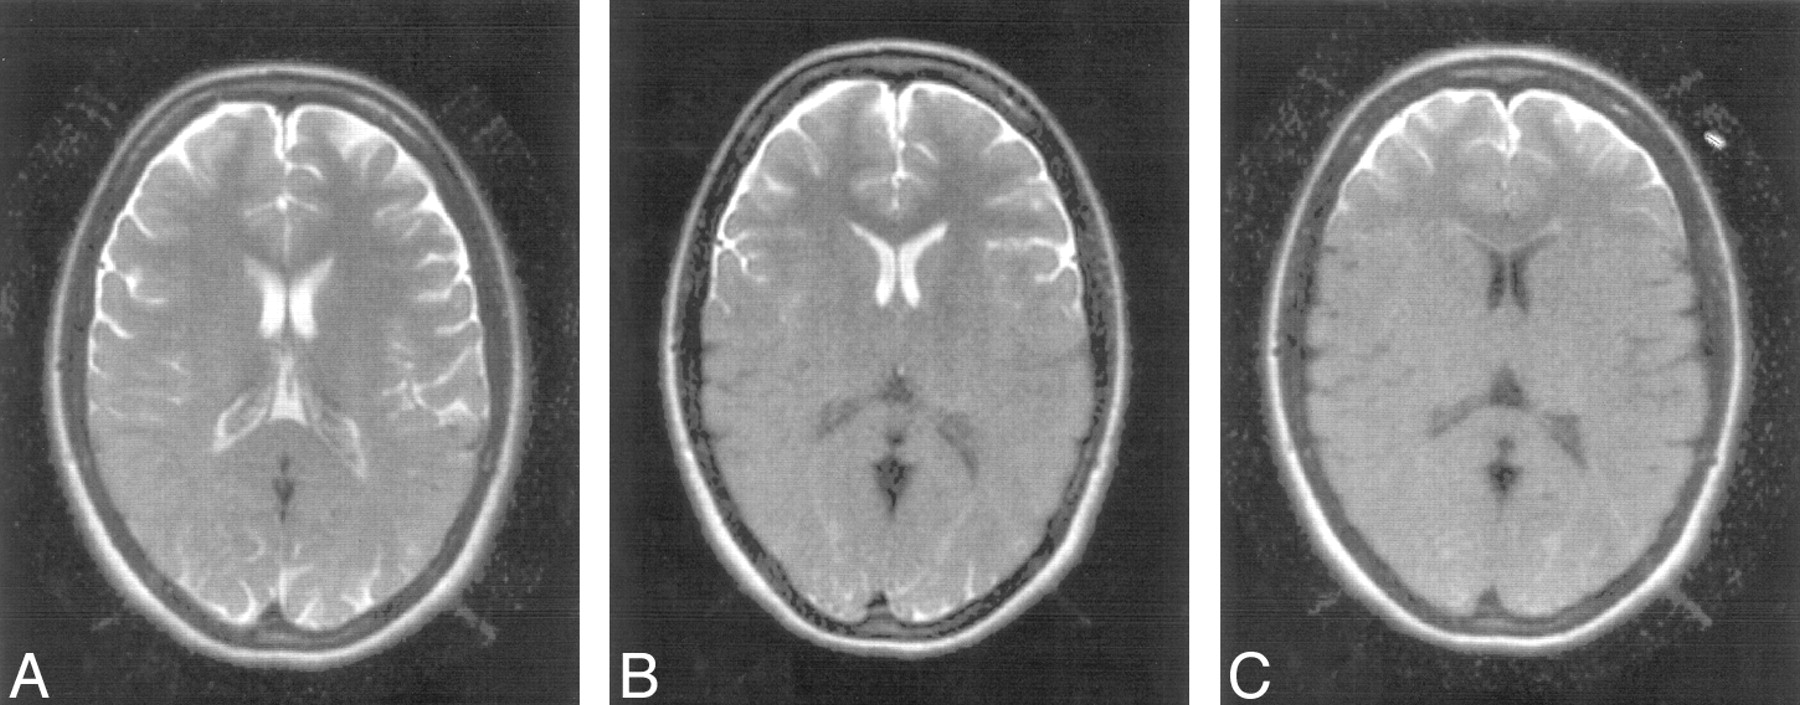

Images from a 53-year-old man with chronic hypertensive encephalopathy and acute mental status change. The patient was agitated and confused. Multisection T2-weighted FSE (repetition time [TR]/echo time [TE]eff = 2800/120 ms) image (A) and standard single-shot, fast spin-echo, fluid-attenuated inversion recovery (SS-FSE-FLAIR) images at different levels (B–D). The T2-weighted FSE image is severely degraded by motion artifact. Images in B to D show no obvious motion artifact, though the patient moved during the acquisition of the images as shown by the change in angulation of the head between sections. In D, obvious high-signal-intensity areas are seen anteriorly in the subarachnoid space. More subtle changes are seen posteriorly. These mimic subarachnoid hemorrhage. A slight increase in gray-white matter contrast is seen in the frontal region in D, consistent with the brain in this region not having experienced the initial inversion pulse. The brain shows extensive white matter change.

In 19 of the 30 patients with acute neurologic syndromes, standard SS-FSE-FLAIR images showed high signal intensity in CSF in regions not associated with pulsatile CSF artifacts such as within the Sylvian fissures and over the convexities of the cerebral hemispheres. Patient motion could be inferred from changes in the orientation of sections as well as by gaps in the section pattern and overlap of sections on most sets of standard SS-FSE-FLAIR images. In each case, conventional T1- and/or T2-weighted images showed motion artifact. In patients who had not had lumbar punctures, it was not possible to be certain that subarachnoid blood or elevated CSF protein levels were not present and had caused the high signal intensity in the CSF. For that reason, attention was focused on the 6 patients with a negative lumbar puncture for blood and xanthochromia and without elevated CSF protein. Images from one of these patients are shown in Fig 5.